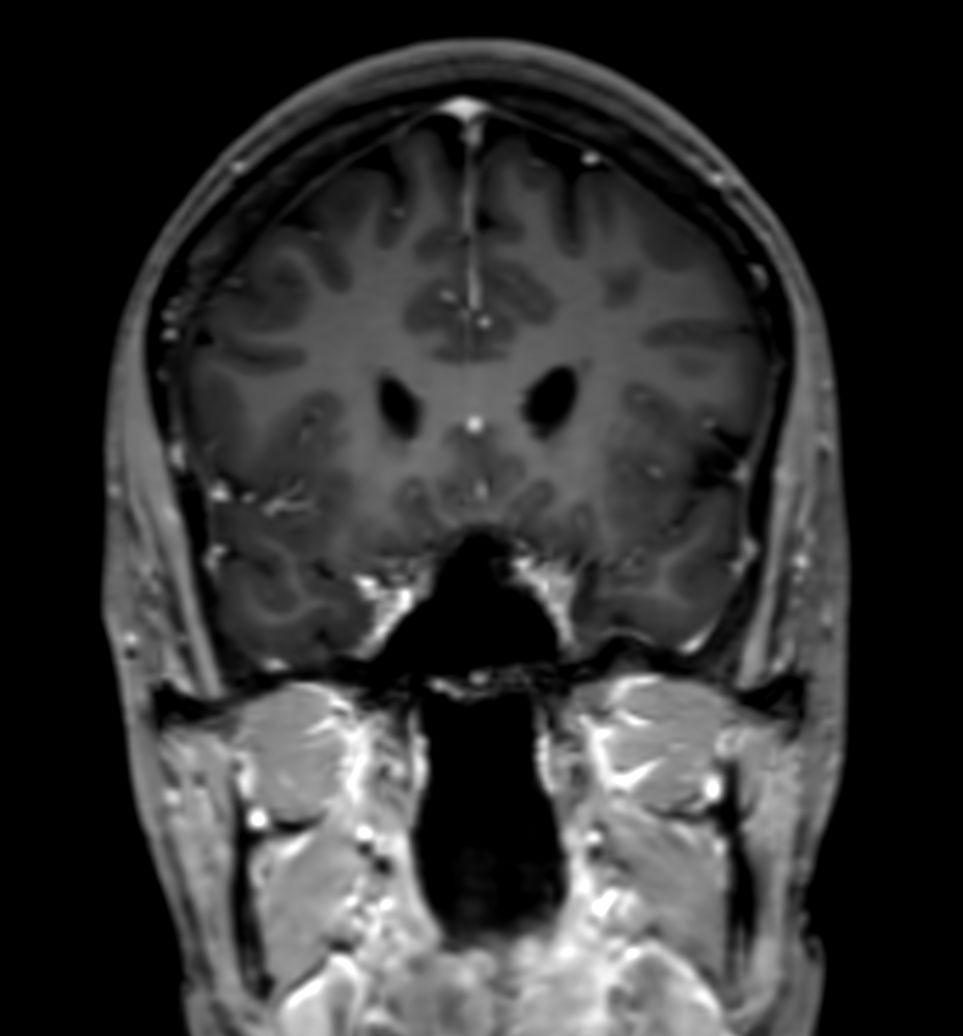

SWI sequence has a high sensitivity to enhance contrast for deoxygenated (venous) blood or calcium deposits. This may help, when used in combination with other clinical information, in the diagnosis of various neurological pathologies. 3D imaging lets you acquire high resolution data in multiple directions in one scan. Isotropic voxel size enables reformats in any plane without loss of resolution. FLAIR* requires offline post processing combining the contrast of 3D FLAIR and 3D SWI EPI into a single image. This enables the visualization of Central Vein Sign, mapping subcortical veins onto 3D FLAIR contrast images.